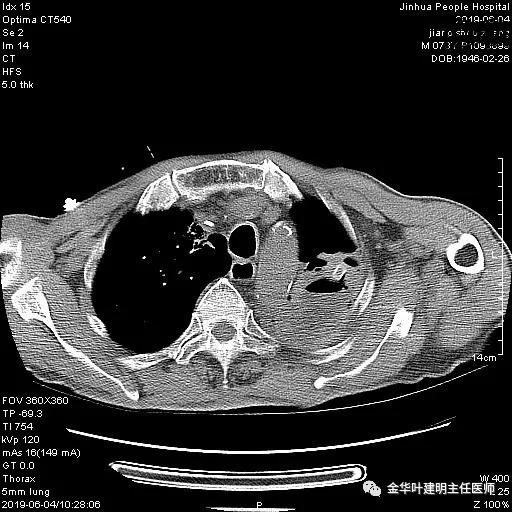

患者,男性,73岁,金华人。因“咳嗽咳痰伴胸闷2月,检查确诊左肺癌1周”入院。气管镜: 气管支气管内较多脓性分泌物,左肺上叶前段管腔新生物,局部活检、毛刷。气管镜病理:(左肺活检)鳞癌。阅胸部CT见左上叶开口处新生物,考虑需左上叶袖式切除及淋巴结清扫。具体CT表现如下:

术前检查冠脉CT示:左冠前降支近段多发钙化斑块伴管腔重度狭窄(约85%),建议DSA检查。但追问病史以往平时无胸痛或胸闷症状,运动试验提示可疑阳性(上斜型压低),活动后胸闷气闭症状不明显,既往否认高血压、糖尿病。所以经过心内科会诊讨论,认为还是可以进行手术。术前冠状动脉CT示: